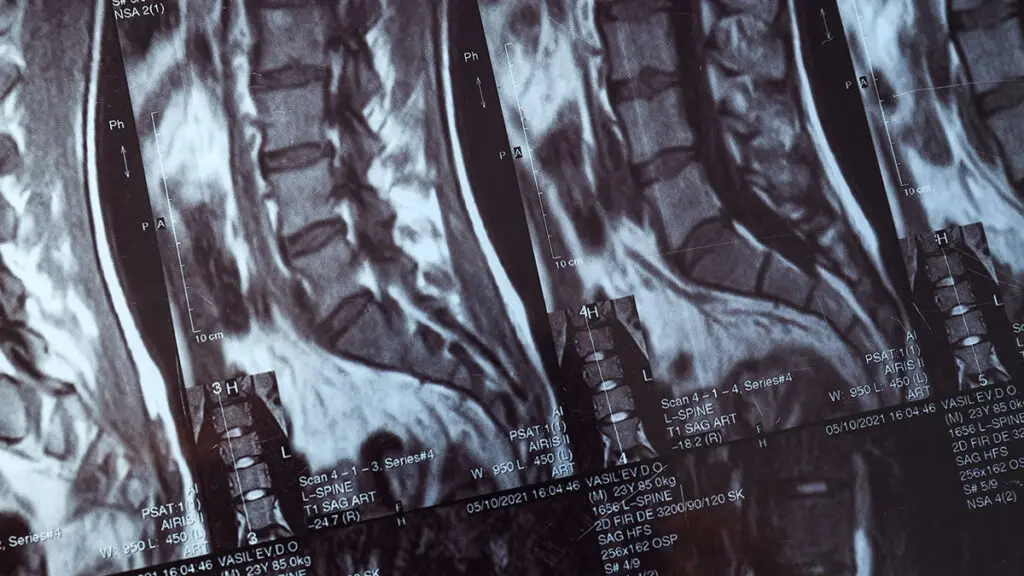

Global Spine Solutions è il centro di riferimento a Roma per chi cerca un specialista mal di schiena con competenze di alto livello in neurochirurgia spinale mininvasiva. Il nostro team multidisciplinare accompagna ogni paziente dalla diagnosi al trattamento, con un approccio personalizzato che integra le tecnologie più avanzate nel campo delle patologie vertebrali e neurologiche.

Affidarsi al giusto specialista mal di schiena fa la differenza. Da Global Spine Solutions trovi professionisti con esperienza pluriennale nelle patologie della colonna vertebrale, capaci di valutare ogni caso in modo accurato e proporre il percorso terapeutico più adeguato, privilegiando ove possibile le soluzioni conservative e mininvasive rispetto alla chirurgia tradizionale.